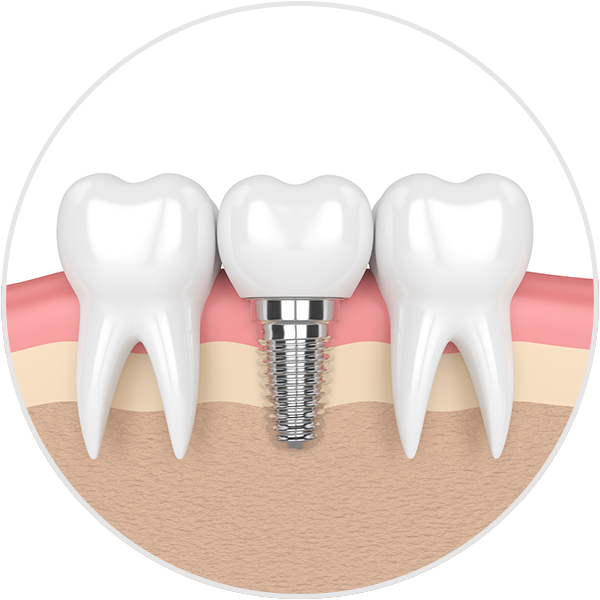

Dental implants are designed to provide a foundation for replacement teeth that look, feel and function like natural teeth. The person who has lost teeth regains the ability to eat virtually anything and can smile with confidence, knowing that teeth appear natural and that facial contours will be preserved.

The implants are tiny titanium posts which are placed into the jaw bone where teeth are missing. The bone bonds with the titanium, creating a strong foundation for artificial teeth. In addition, dental implants can help preserve facial structure, preventing the bone deterioration which occurs when teeth are missing.

Dental implants are metal anchors, which act as tooth root substitutes. They are surgically placed into the jaw bone. Small posts are then attached to the implant, which protrude through the gums. These posts provide stable anchors for artificial replacement teeth.

For most patients, the placement of dental implants involves two surgical procedures. First, dental implants are placed within your jaw bone. For the first three to six months following surgery, the implants are beneath the surface of the gums, gradually bonding with the jaw bone. You should be able to wear temporary dentures and eat a soft diet during this time. At the same time, your restorative dentist designs the final bridgework or denture, which will ultimately improve both function and aesthetics.

After the dental implant has bonded to the jaw bone, the second phase begins. The surgeon will uncover the implants and attach a small healing collar. Drs. Tsang, Godfrey, Hwang or Han can then start making your new teeth. An impression must be taken. Then posts or attachments can be connected to the implants. The replacement teeth are then made over the posts or attachments. The entire procedure usually takes six to eight months. Most patients do not experience any disruption in their daily life.